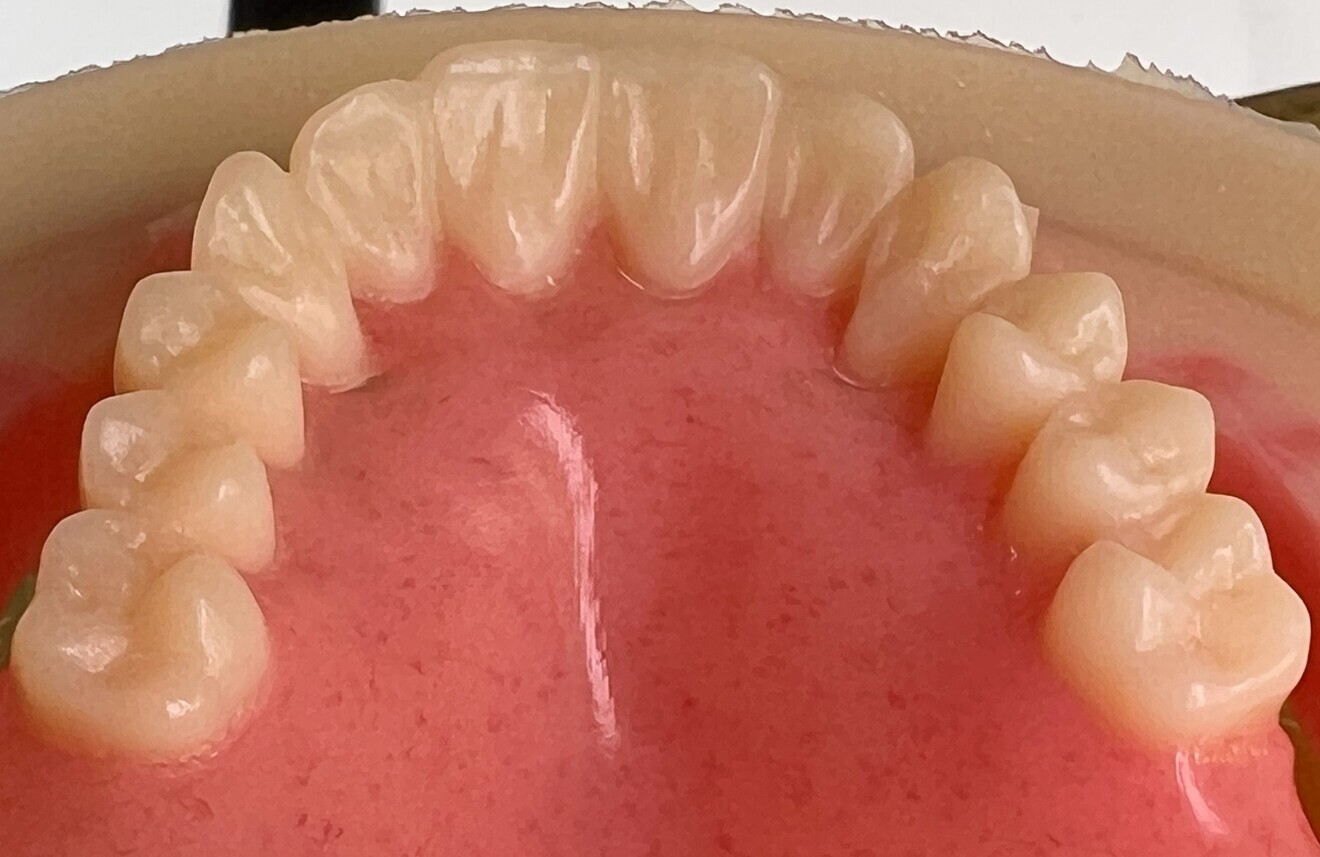

The 3D files of the prostheses were exported to the Ivotion denture system’s specific CAM module (Ivoclar; Figs. 4–6). The prostheses were milled using the Ivoclar-exclusive Shell Geometry processing capability of the R5 (Figs. 7–9). In 4 hours, the complete maxillary and mandibular prostheses had been fabricated (Fig. 10). For the maxillary prosthesis, we immediately relined it after removing the framework that had been screwed to the prosthesis and then screwed it in (Fig. 11). Re-evaluation with a digital facebow and data comparison were made possible by remote control (Figs. 12 & 13).

Fig. 10: Extremely high level of morphological and surface detail produced with the simultaneous monolithic milling of the pink aesthetics and the teeth.